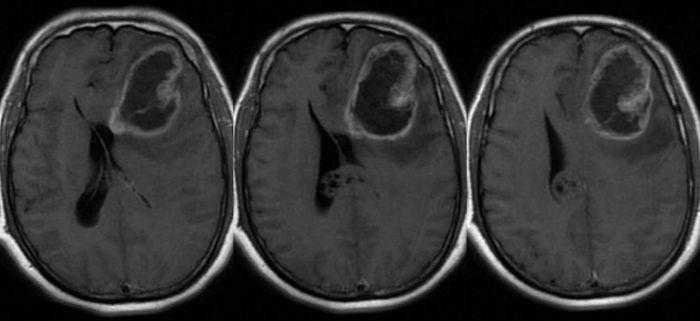

يعتبر الورم الأرومي الدبقي – Glioblastoma هو الشكل الأكثر شيوعا من سرطانات الدماغ وغالبا ما تكون قاتلة، ومعظم المرضى يموتون في غضون عامين من التشخيص. وتماما مثل الأنسجة الطبيعية والصحية، فإن نمو وتطور الخلايا الأرومية تحركه الخلايا الجذعية التي تتكاثر وتؤدي إلى تكون خلايا ورم أخرى. وتعتبر الخلايا الجذعية الأرومية من الخلايا التي يصعب أن تقتل لأن بإمكانها تجنب الجهاز المناعي في الجسم ومقاومة العلاج الكيميائي والإشعاعي، وبالتالي فإن قتل هذه الخلايا أمر حيوي لمنع الأورام الجديدة من التكون مرة أخرى بعد إزالة الورم الأصلي جراحيا.

ووجد الباحثون أن فيروس زيكا قد أصاب وقتل خلايا جذعية دبقية تم استخلاصها من أحد المرضى بشكل تفضيلي، مقارنة مع أنواع الخلايا الدبقية الأخرى أو الخلايا العصبية الطبيعية. وأيضا عندما تم حقن فئران مصابة بورم عنيف من الأورام الدبقية، لاحظ الباحثون أن الفيروس قد أبطأ من نمو الورم ومددت بشكل كبير من مدى عمر هذه الفئران.